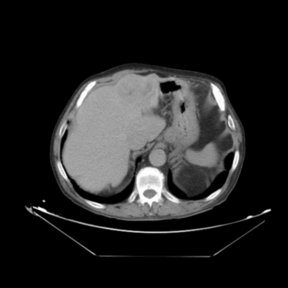

In addition to the previous measurements, the visual outcomes of two of the experiments are shown in [[#img-3|Figures 3]] and [[#img-4|4]], whose purpose is to highlight the most illustrative differences (from a medical point of view) between the results provided by the compared methods. In  [[#img-3|Figure 3]], we observe a normal size of the liver, with discretely irregular contours and homogeneous signal intensity. In hepatic segment II, there is a lesion of 40 mm of maximum axis, encapsulated and with well-defined contours and heterogeneous enhancement in arterial phase (after administration of intravenous contrast), suggestive of hepatocellular carcinoma (HCC). In this slice of the CT scan, we can also observe the aorta that shines in the arterial phase, the lower area of the stomach and the upper area of the spleen. In  [[#img-4|Figure 4]], the liver has a normal size with discretely irregular contours in relation to changes due to chronic liver disease. In hepatic segment IV, a 36 mm diameter focal lesion is identified, which has arterial phase enhancement with a small area of necrosis of 13 mm; it corresponds to a HCC previously chemoembolized with partial necrosis. In this slice of CT, we can also observe the aorta, the gastric chamber and the spleen. When comparing the two methods under study, it can be seen how in  [[#img-3|Figure 3]] the resulting registered datasets are very similar. However, looking closely, it can be noticed that in the right part of the image (left side of the patient) the shape and width of the structures corresponding to the stomach and the spleen in  [[#img-3|Figure 3]](d) match better those in the reference dataset. Likewise, the part of the rib at the upper right of the image is more similar to the same region in the reference dataset by using the proposed method. Regarding the experiment shown in  [[#img-4|Figure 4]], it can be easily appreciated how the geometrical matching (with respect to the reference dataset,  [[#img-4|Figure 4]](a)) of the structures in the right side of the image (specially the gastric chamber) is visually more satisfactory in  [[#img-4|Figure 4]](d). Moreover, the area of tumor necrosis which results from the proposed method is also slightly better aligned.

In addition to the previous measurements, the visual outcomes of two of the experiments are shown in figures Fig.[[#img-3|3]] and Fig.[[#img-4|4]], whose purpose is to highlight the most illustrative differences (from a medical point of view) between the results provided by the compared methods. In Fig.[[#img-3|3]], we observe a normal size of the liver, with discretely irregular contours and homogeneous signal intensity. In hepatic segment II, there is a lesion of 40 mm of maximum axis, encapsulated and with well-defined contours and heterogeneous enhancement in arterial phase (after administration of intravenous contrast), suggestive of hepatocellular carcinoma (HCC). In this slice of the CT scan, we can also observe the aorta that shines in the arterial phase, the lower area of the stomach and the upper area of the spleen. In Fig.[[#img-4|4]], the liver has a normal size with discretely irregular contours in relation to changes due to chronic liver disease. In hepatic segment IV, a 36 mm diameter focal lesion is identified, which has arterial phase enhancement with a small area of necrosis of 13 mm; it corresponds to a HCC previously chemoembolized with partial necrosis. In this slice of CT, we can also observe the aorta, the gastric chamber and the spleen. When comparing the two methods under study, it can be seen how in Fig.[[#img-3|3]] the resulting registered datasets are very similar. However, looking closely, it can be noticed that in the right part of the image (left side of the patient) the shape and width of the structures corresponding to the stomach and the spleen in Fig.[[#img-3|3]](d) match better those in the reference dataset. Likewise, the part of the rib at the upper right of the image is more similar to the same region in the reference dataset by using the proposed method. Regarding the experiment shown in Fig.[[#img-4|4]], it can be easily appreciated how the geometrical matching (with respect to the reference dataset, Fig.[[#img-4|4]](a)) of the structures in the right side of the image (specially the gastric chamber) is visually more satisfactory in Fig.[[#img-4|4]](d). Moreover, the area of tumor necrosis which results from the proposed method is also slightly better aligned.